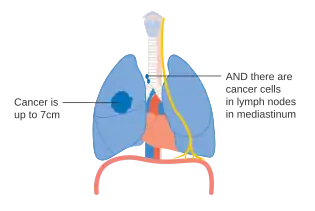

- Diagrams of main features of staging

One option for stage IIB lung cancer, with T2b; but if tumor is within 2 cm of the carina, this is stage 3 -

Stage IIIA lung cancer -

Stage IIIA lung cancer, if there is one feature from the list on each side -

Stage IIIB lung cancer -

Stage IV lung cancer